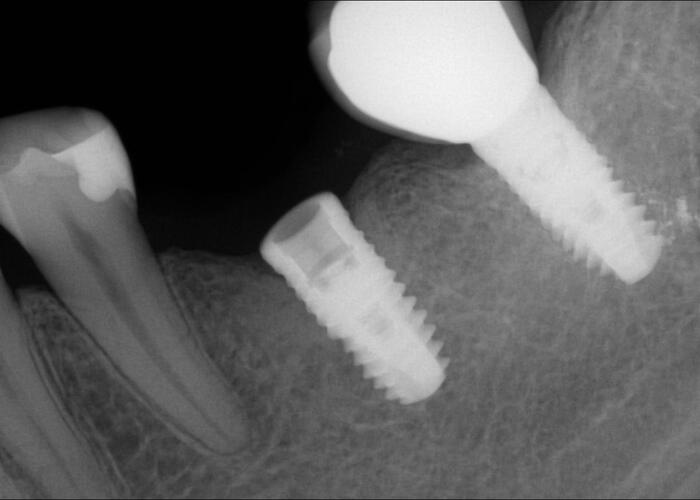

И тут начинается самое интересное. Что такое абатмент мы выяснили из картинки выше, это переходный элемент между коронкой и имлпантатом. Так вот по всем технологиям и нормам он должен быть титановым. Как контрастирует титан на рентгеновском снимке вы можете заметить, посмотрев на имплантат. Видите разницу между 6м и 7м имплантатом?

Так вот абатмент, который вставляется в имплантат из другого материала. Вероятнее всего это кобальт-хромовый сплав. Такие штуки изготавливаются литьевым методом. Все мы знаем, что металл при нагревании расширяется, а остывая сжимается, дает усадку. Соединение имплантат- абатмент должно быть четким. Важны даже микроны. В данном случае наверняка была микроподвижность в этом соединении, высокая нагрузка на винт, в связи с чем он и сломался.

На фото ниже виден шестигранник, обратите внимание какой он шероховатый. Он должен быть отполированным, гладким. (К слову, о той микроподвижности, про которую я говорил выше)

Сравнение абатмента из кобальт-хрома и титана: